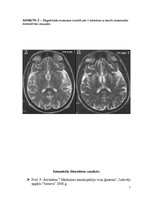

Kreicfelda - Jakoba slimība

Nervu sistēmas slimības